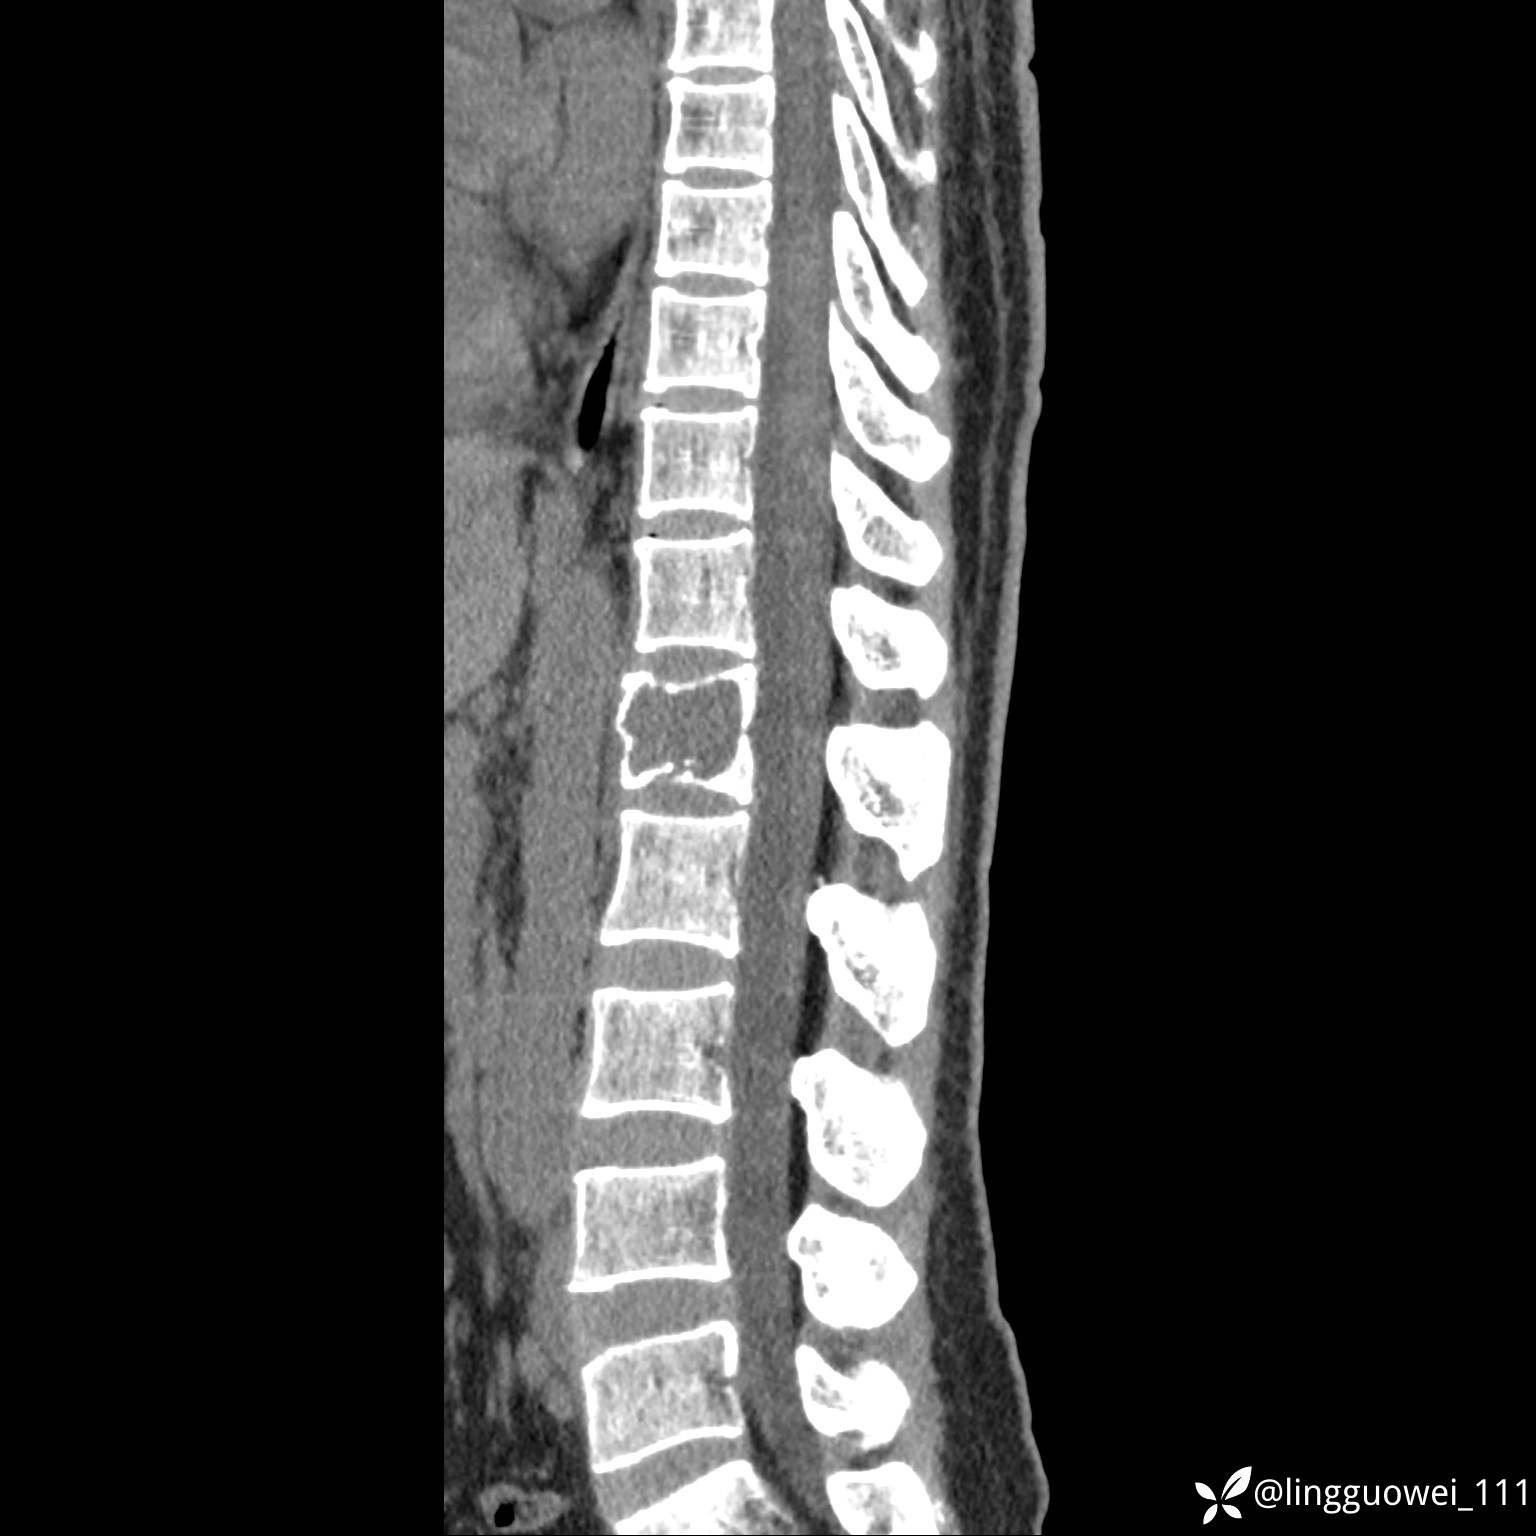

病例女,39岁,腰痛来诊,只有CT可能要鉴别诊断,而MR可以定性吗?

患者性别:女

患者年龄:39岁

主诉:腰痛